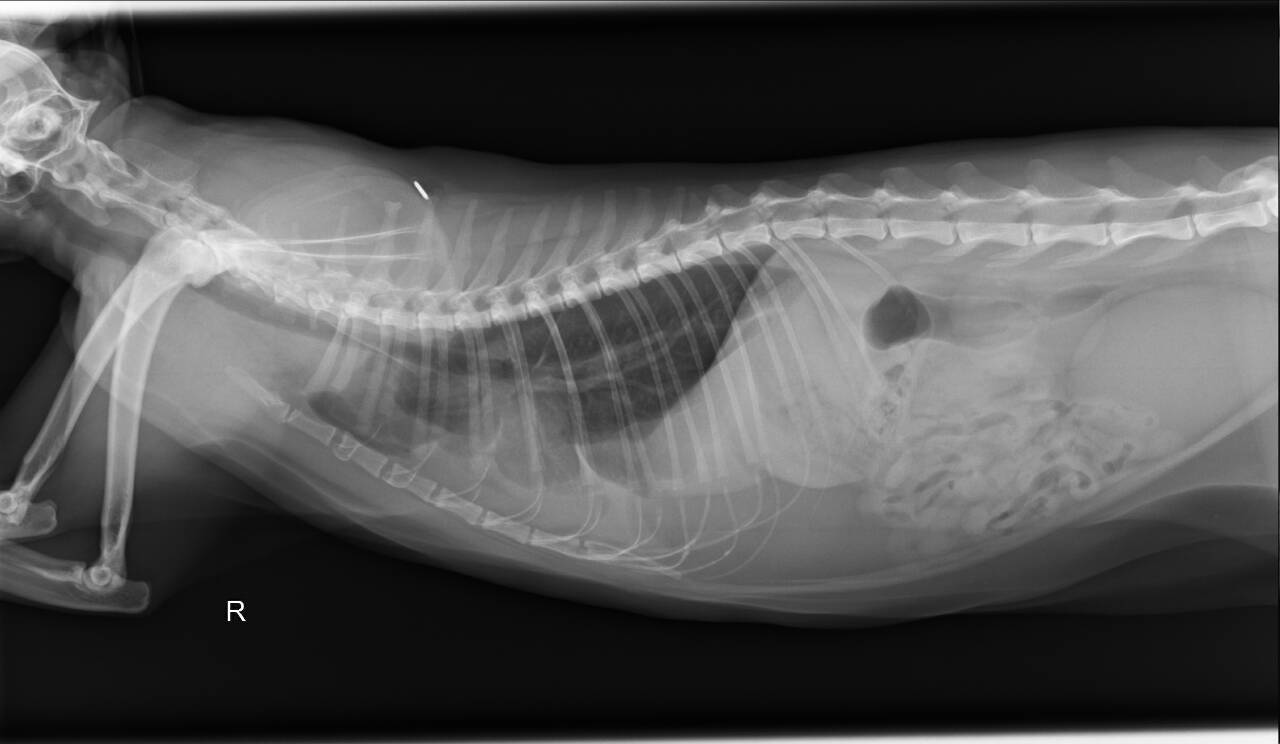

長青醫師詳細觸診、血檢、X光、超音波、抽胸水檢驗(下午約抽出18ml)、眼球葡萄膜炎檢測。

血液檢驗跟胸水檢驗都有發現不正常細胞(病菌),必須再更進一步檢查膿胸的發生原因。

住院期間僅用抗生素治療未使用干擾素,胸水未再激增也未再急喘, 醫師逐一排除罹患腹膜炎及淋巴腫瘤的可能性, 確認為創傷性膿胸。